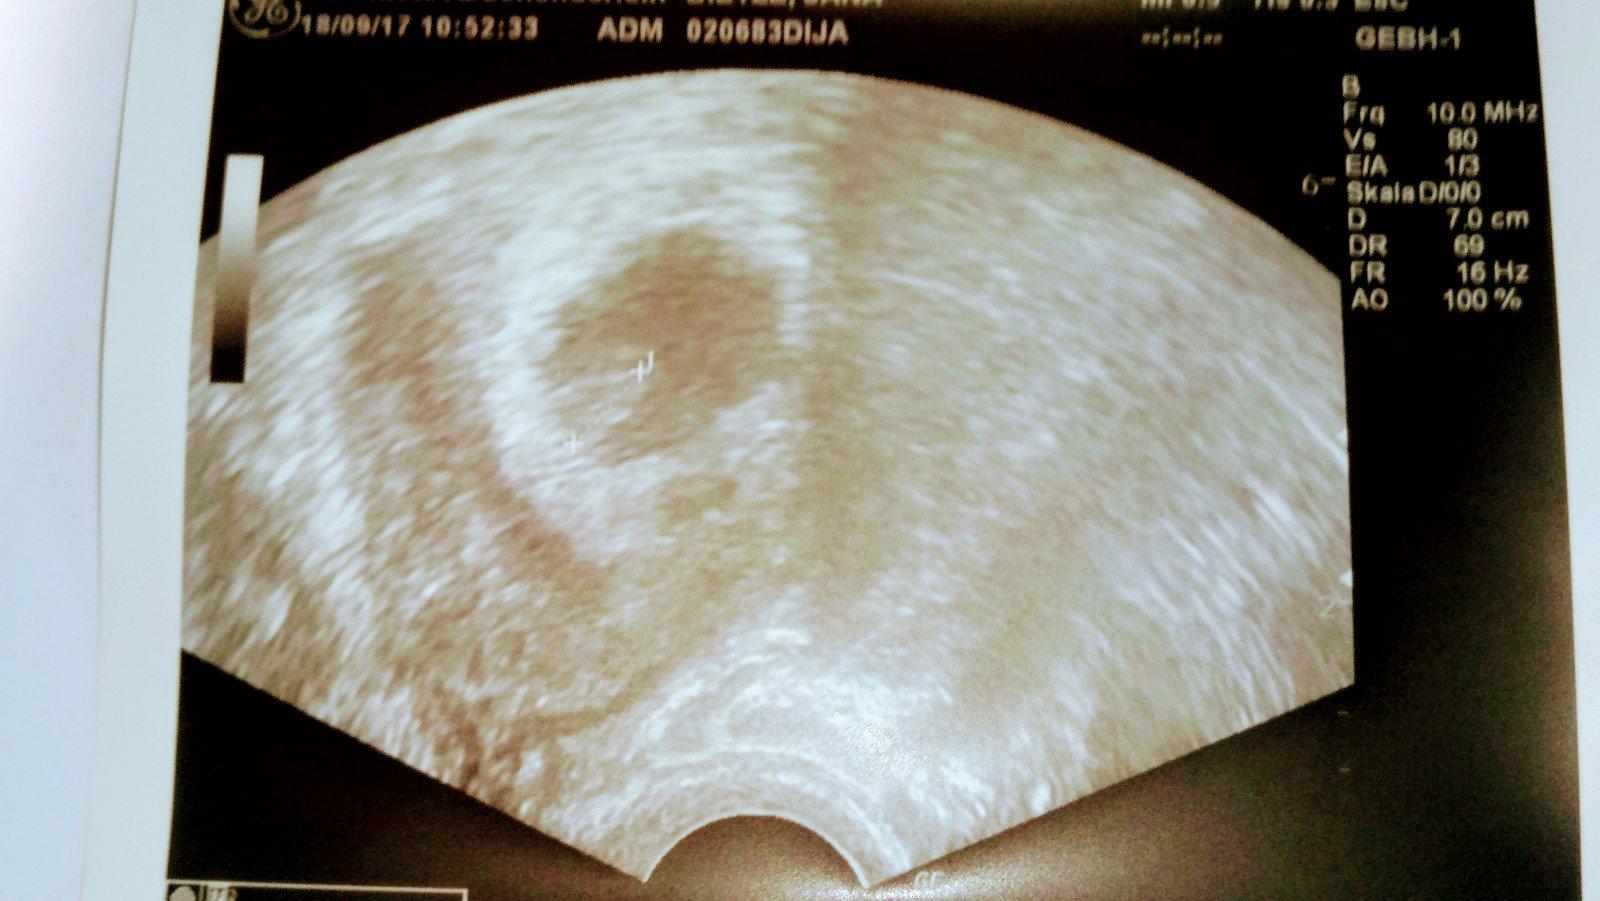

Holky asik jsem se nepochlubila dneska u Dr 6+6podle ultrazvuku podle ms 7+0❤krasne bilo 9.10 dostaneme prukazku a mam se setrit napsala MI dalsich 90tablet utrogestanu a prý je budu brat minimalne do 12tydne :sleepin